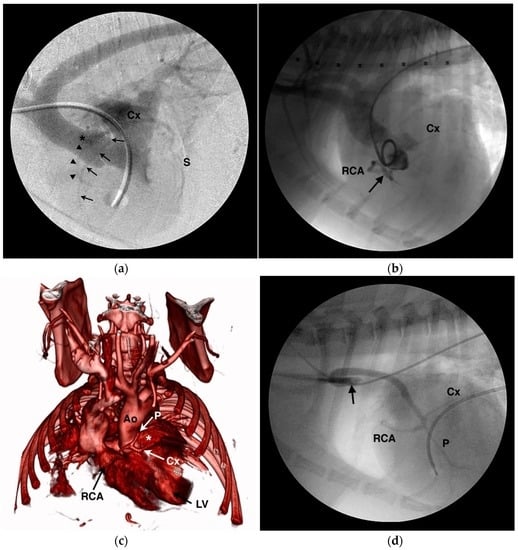

4.1. Anomalous Origin from the Aorta

4.2. Anomalous Origin from the Pulmonary Trunk

- Navalon, I.; Pradelli, D.; Bussadori, C.M. Transesophageal echocardiography to diagnose anomalous right coronary artery type r2a in dogs. J. Vet. Cardiol. 2015, 17, 262–270. [Google Scholar] [CrossRef] [PubMed]

- Visser, L.C.; Scansen, B.A.; Schober, K.E. Single left coronary ostium and an anomalous prepulmonic right coronary artery in 2 dogs with congenital pulmonary valve stenosis. J. Vet. Cardiol. 2013, 15, 161–169. [Google Scholar] [CrossRef] [PubMed]

- Laborda-Vidal, P.; Pedro, B.; Baker, M.; Gelzer, A.R.; Dukes-McEwan, J.; Maddox, T.W. Use of ECG-gated computed tomography, echocardiography and selective angiography in five dogs with pulmonic stenosis and one dog with pulmonic stenosis and aberrant coronary arteries. J. Vet. Cardiol. 2016, 18, 418–426. [Google Scholar] [CrossRef] [PubMed]

- Waterman, M.I.; Abbott, J.A. Novel coronary artery anomaly in an English bulldog with pulmonic stenosis. J. Vet. Intern. Med. 2013, 27, 1256–1259. [Google Scholar] [CrossRef] [PubMed]